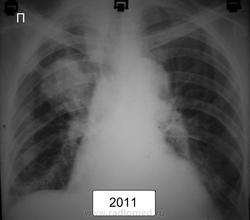

Ж.1938г.р. жалоб нет, более ранние рентг.описания - туберкулома

По-моему это типичный периферический рак

С уже "централизацией". Вопрос-больной наблюдается не мало-других мыслей кроме туберкуломы не было и он нигде больше не обследовался? Или это неизвестно?

был периферический кадато, стал централизоваться , пророс по бронхам как по рельсам :-)

должны были наблюдать в динамике , но характер тени уж совсем не за туберкулому!